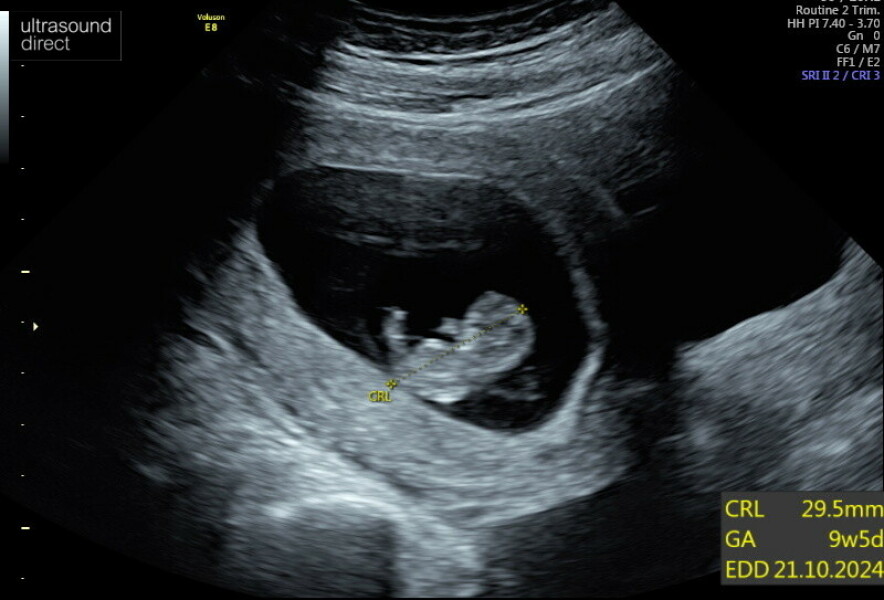

Joey2011 · 23/03/2024 15:12

So I had a 10week scan today. All doing very well. And measuring at 9w+6 so spot on. Baby had hiccups 🥰 and was right wriggling round.

Wish I could show you the videos. I can't stop watching it 😁